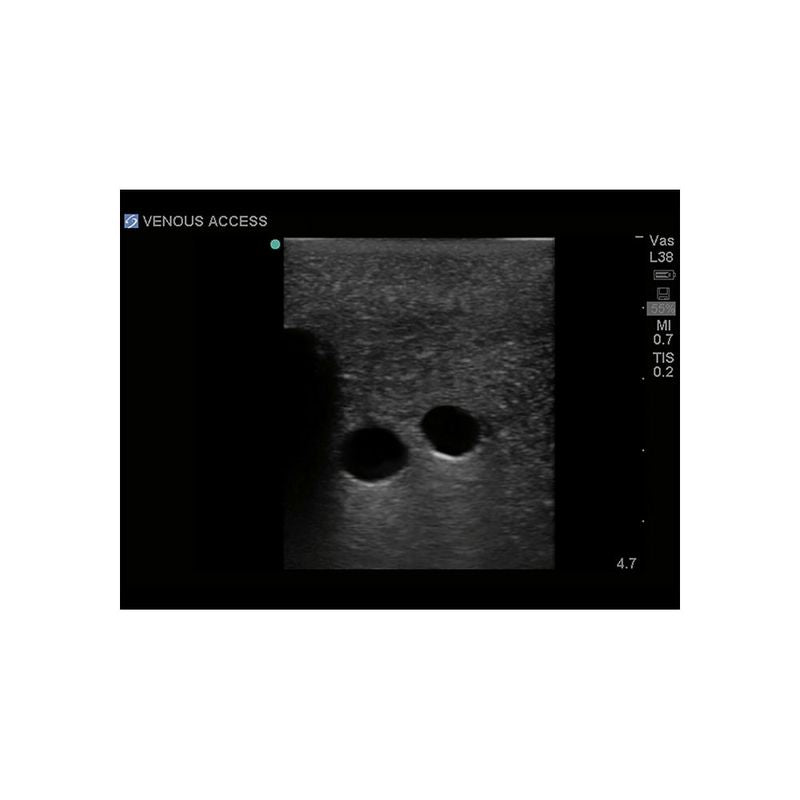

Replacement tissue insert for Central Line and Regional Anesthesia Model (BPHNB670 series).-